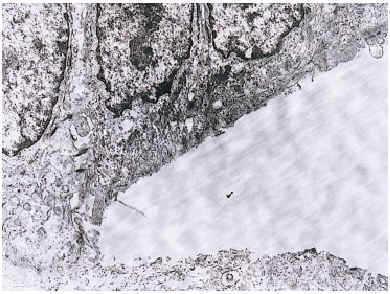

En el estudio histológico de una biopsia de una ampolla cutánea se observó un despegamiento dermo-epidérmico con escaso componente inflamatorio. La tinción con PAS reveló que la membrana basal quedaba adherida al techo de la ampolla. En el estudio ultraestructural se apreció que se producía un despegamiento por debajo de la membrana basal (Fig. 2). El niño fue tratado con mupirocina tópica y vendajes, con buena evolución clínica. A los 6 meses la aplasia cutánea había reepitelizado, dejando una cicatriz atrófica que se acompañaba de múltiples quistes miliares en la cicatriz y en el dorso de ambas manos (Fig. 1 B).

FIG. 2.--Microscopia electrónica que muestra un despegamiento ampolloso por debajo de la membrana basal.